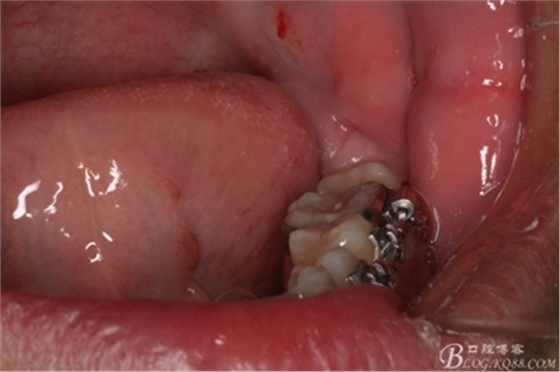

圖3.術(shù)前左側(cè)下頜口內(nèi)照片:37近中阻生,38口內(nèi)看不到。